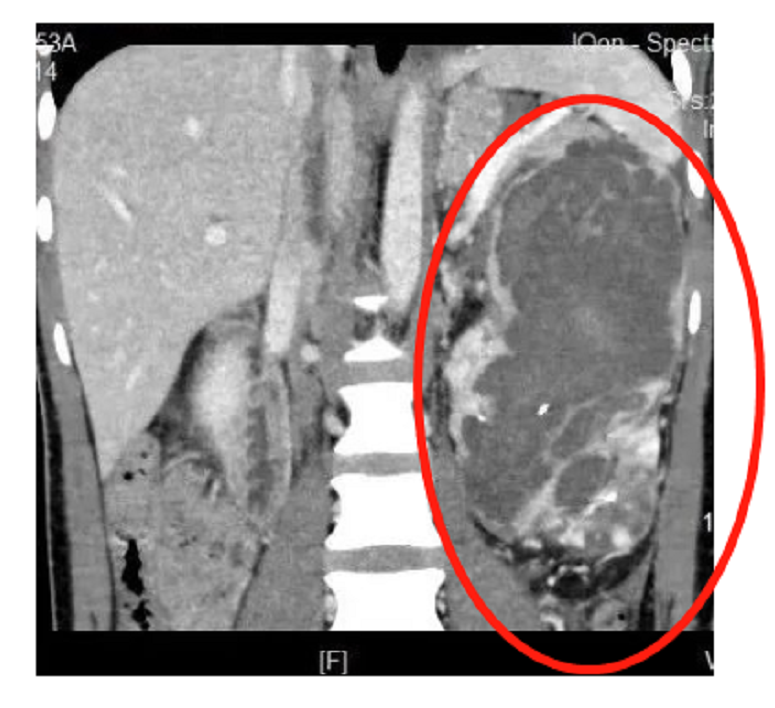

入院后,薛学义教授团队对陈先生的肿瘤生长情况及肿瘤负荷进行全面地重新评估,发现其左肾恶性肿瘤体积巨大,同时合并破裂出血且已经伴有下腔静脉、左肾静脉、左睾丸静脉癌栓,且癌栓已经穿越膈肌蔓延至右心房入口处。

▲画圈位置为肿瘤

考虑到患者年龄轻及希望积极治疗的意愿,薛学义教授团队对他进行了全面评估,在心外科、肝胆胰外科、麻醉科、超声影像科、介入科等多学科MDT之后,结合影像学情况,为患者详细制定了心脏不停跳情况下行根治左肾切除术及IV级癌栓取出术方案。